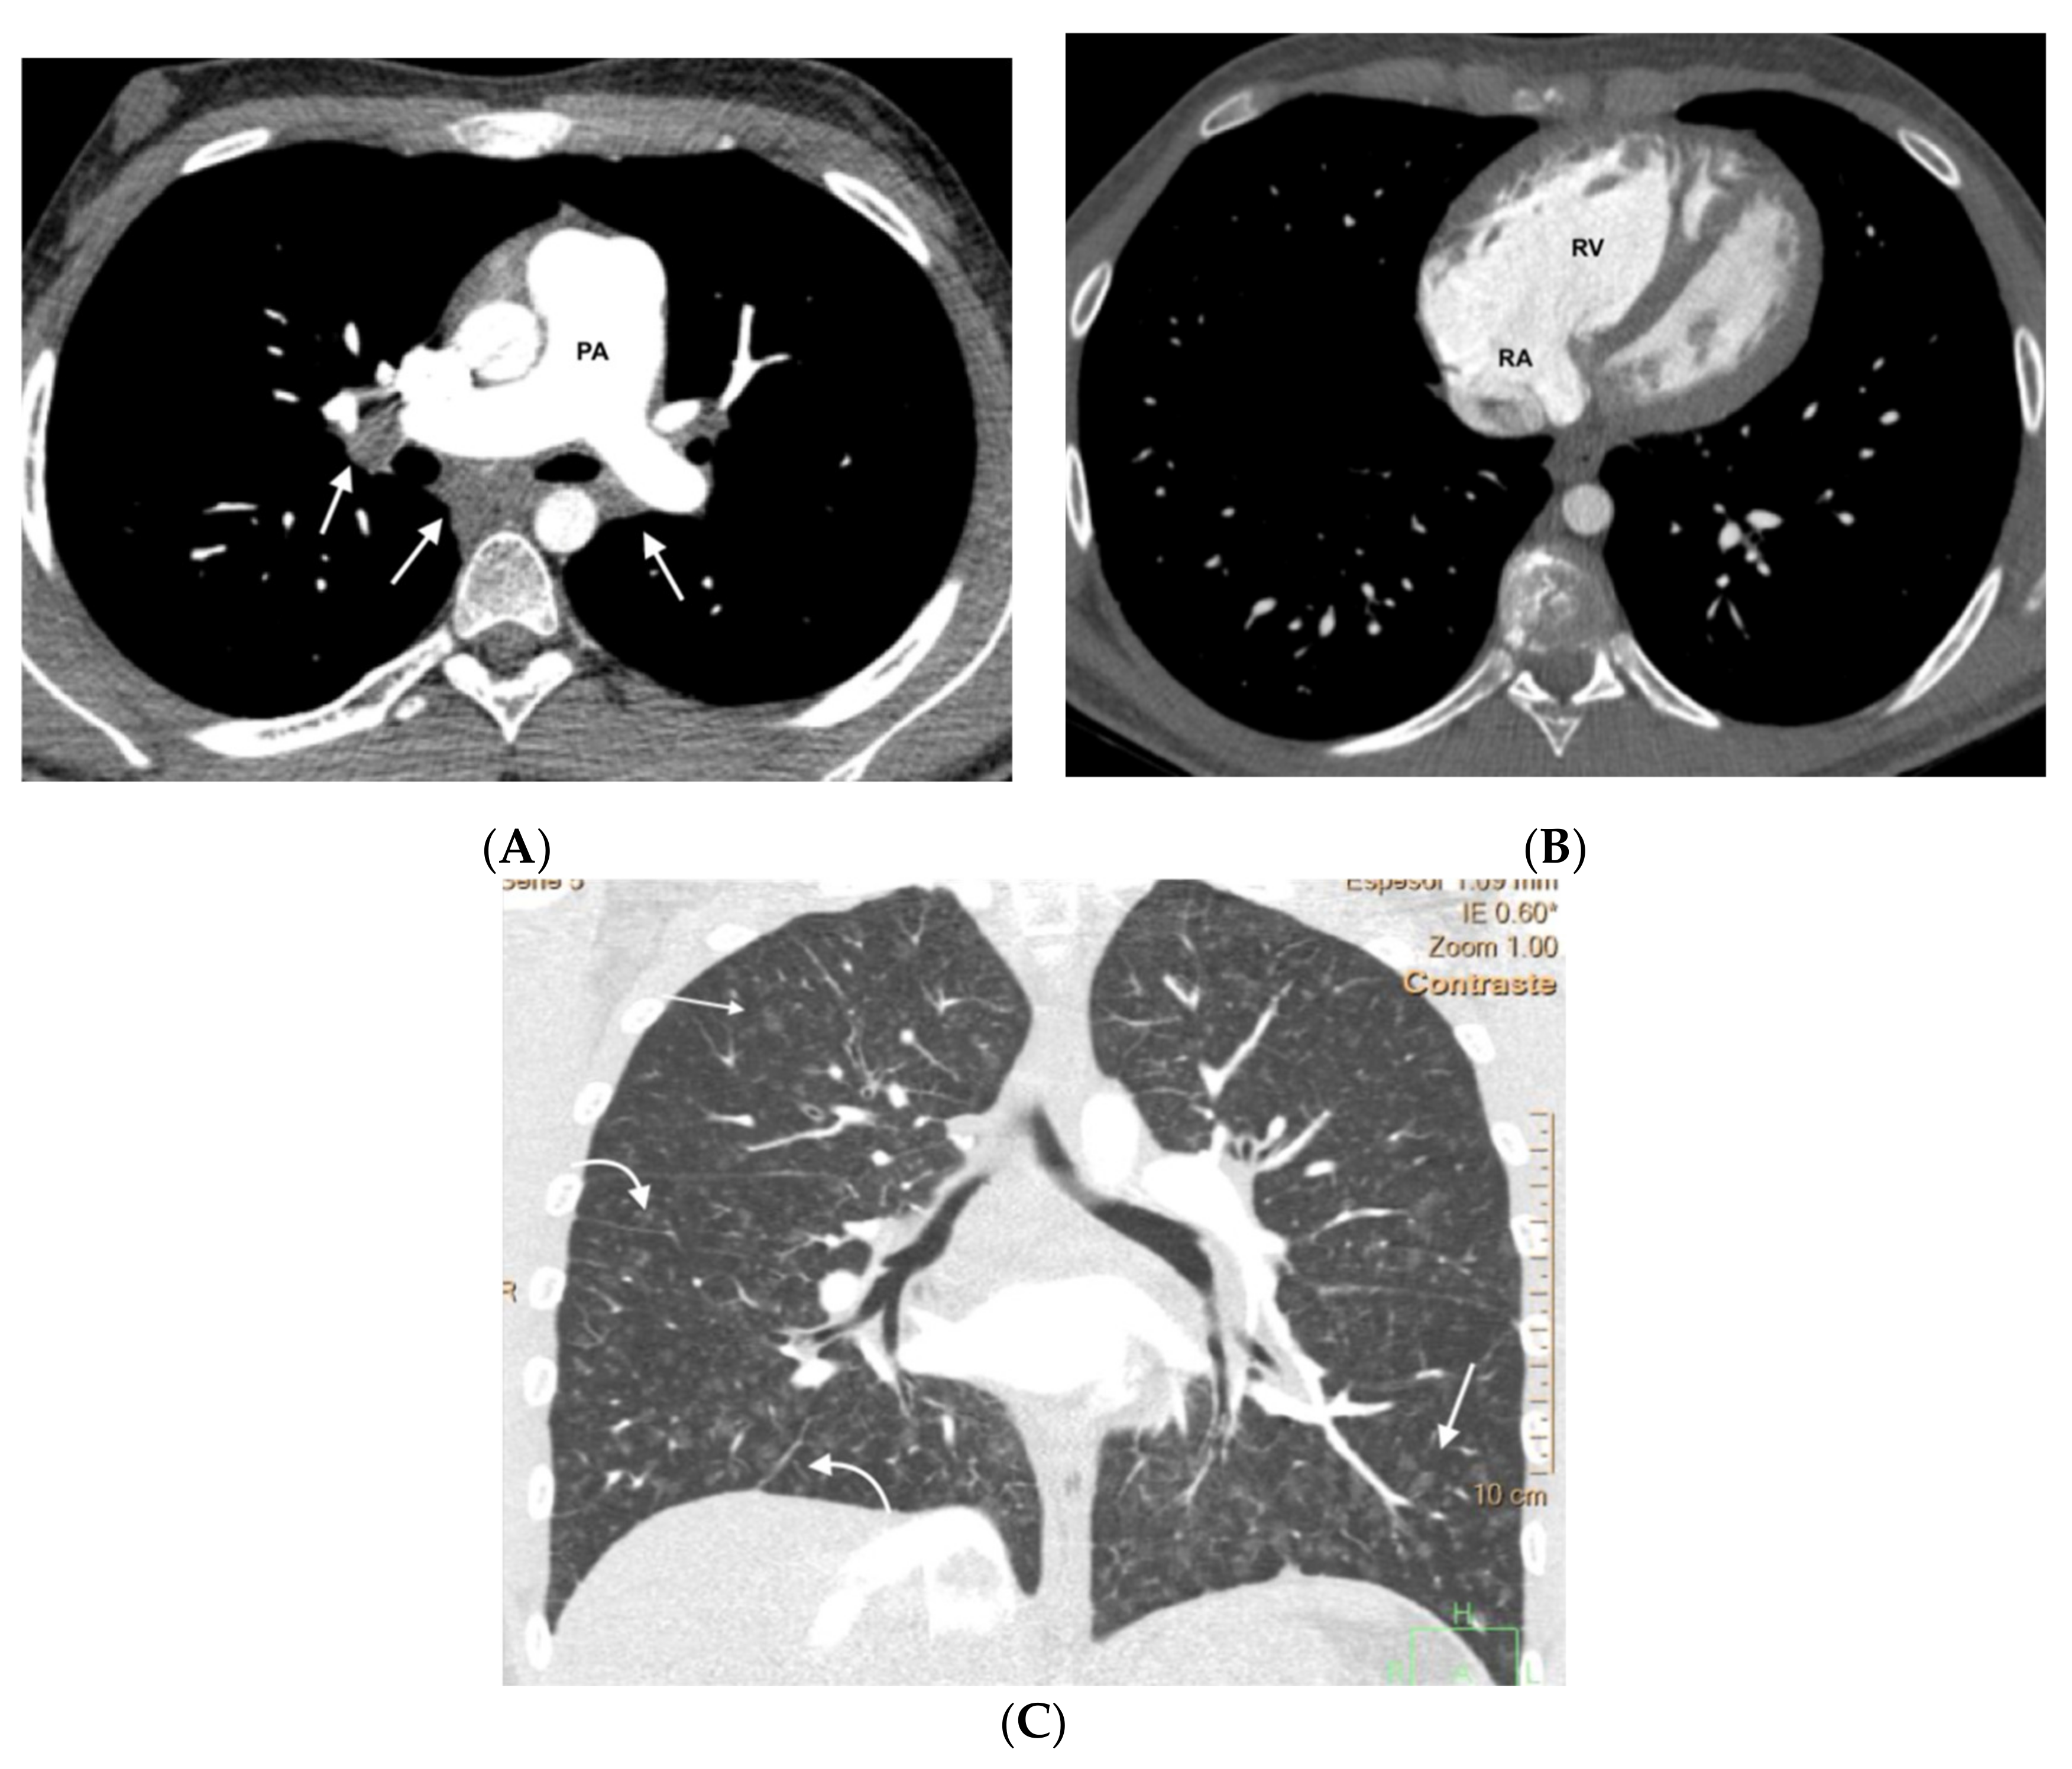

Figure 4.

Fifty-five-year-old woman with sporadic PVOD histologically diagnosed after double lung transplantation. The patient had three typical MDCT findings and in situ thrombus in the left main pulmonary artery (normal ventilation-perfusion scintigraphy excluded CTEPH). (A) Dilation of the pulmonary artery (PA) trunk with thrombus in situ in the left main pulmonary artery (arrows); (B) ground-glass centrilobular nodules in both upper lobes (arrows) and septal lines (short arrows); (C) left hilar adenopathy (arrow). PA: pulmonary artery.

Figure 5.

Forty-seven-year-old woman with sporadic PVOD and three typical findings. (A) Ground glass parenchymal involvement with central geographic distribution (circle) and peripheral centrilobular (curved arrows). Septal lines in basal regions of both lungs (straight arrows); (B) mediastinal lymphadenopathy in the lower right paratracheal location (short arrow) and prevascular (arrow). Right pleural effusion (asterisk).